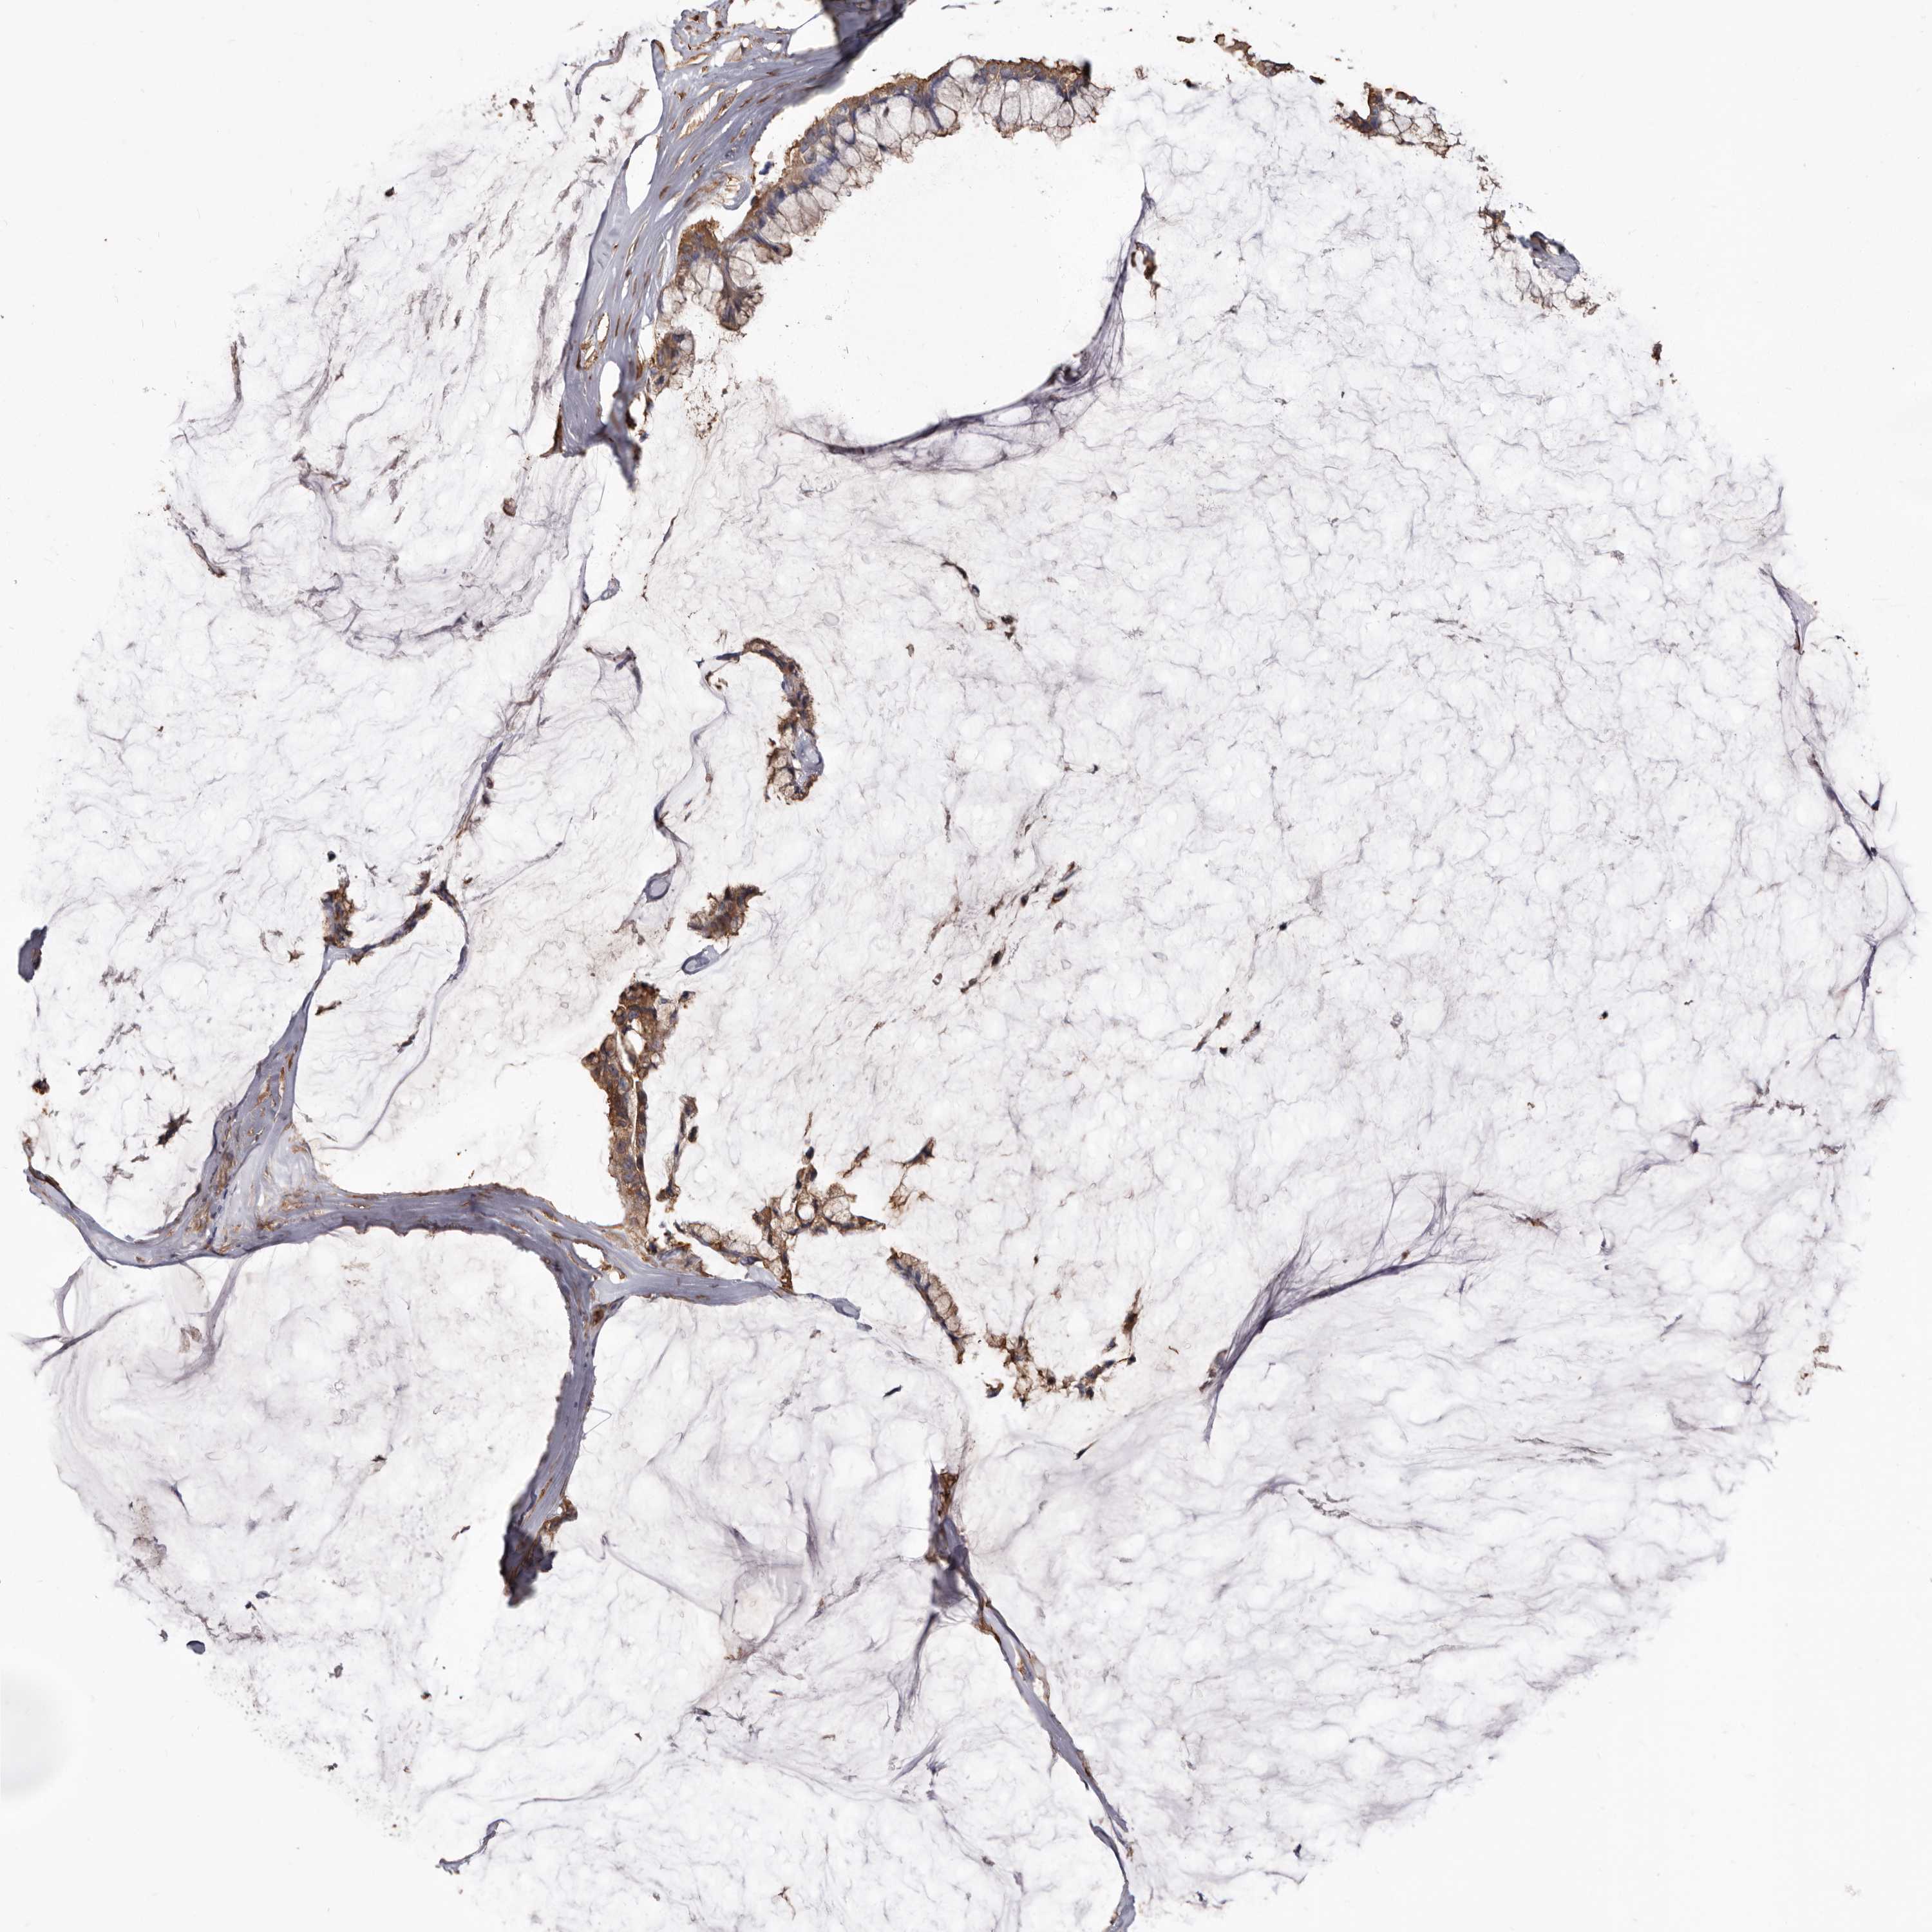

OVARIAN CANCER - Protein expressioni

A mouse-over function shows sample information and annotation data. Click on an image to view it in a full screen mode. Samples can be filtered based on level of antibody staining by selecting one or several of the following categories: high, medium, low and not detected. The assay and annotation is described here.

Note that samples used for immunohistochemistry by the Human Protein Atlas do not correspond to samples in the TCGA dataset.

Antibody stainingi

Antibody staining in the annotated cell types in the current human tissue is reported as not detected, low, medium, or high, based on conventional immunohistochemistry profiling in selected tissues. This score is based on the combination of the staining intensity and fraction of stained cells.

Each image is clickable and will lead to virtual microscopy that enables deeper exploration of all samples and also displays staining intensity scores, fraction scores and subcellular localization as well as patient and tissue information for each sample.

Antibody HPA029501

Antibody CAB019421

Staining

High

Medium

Low

Not detected

Intensity

Strong

Moderate

Weak

Negative

Quantity

>75%

75%-25%

<25%

None

Location

Nuclear

Cytoplasmic/membranous

Cytoplasmic/membranous,nuclear

Cystadenocarcinoma, serous, NOS

Carcinoma, endometroid

Cystadenocarcinoma, mucinous, NOS

Carcinoma, NOS